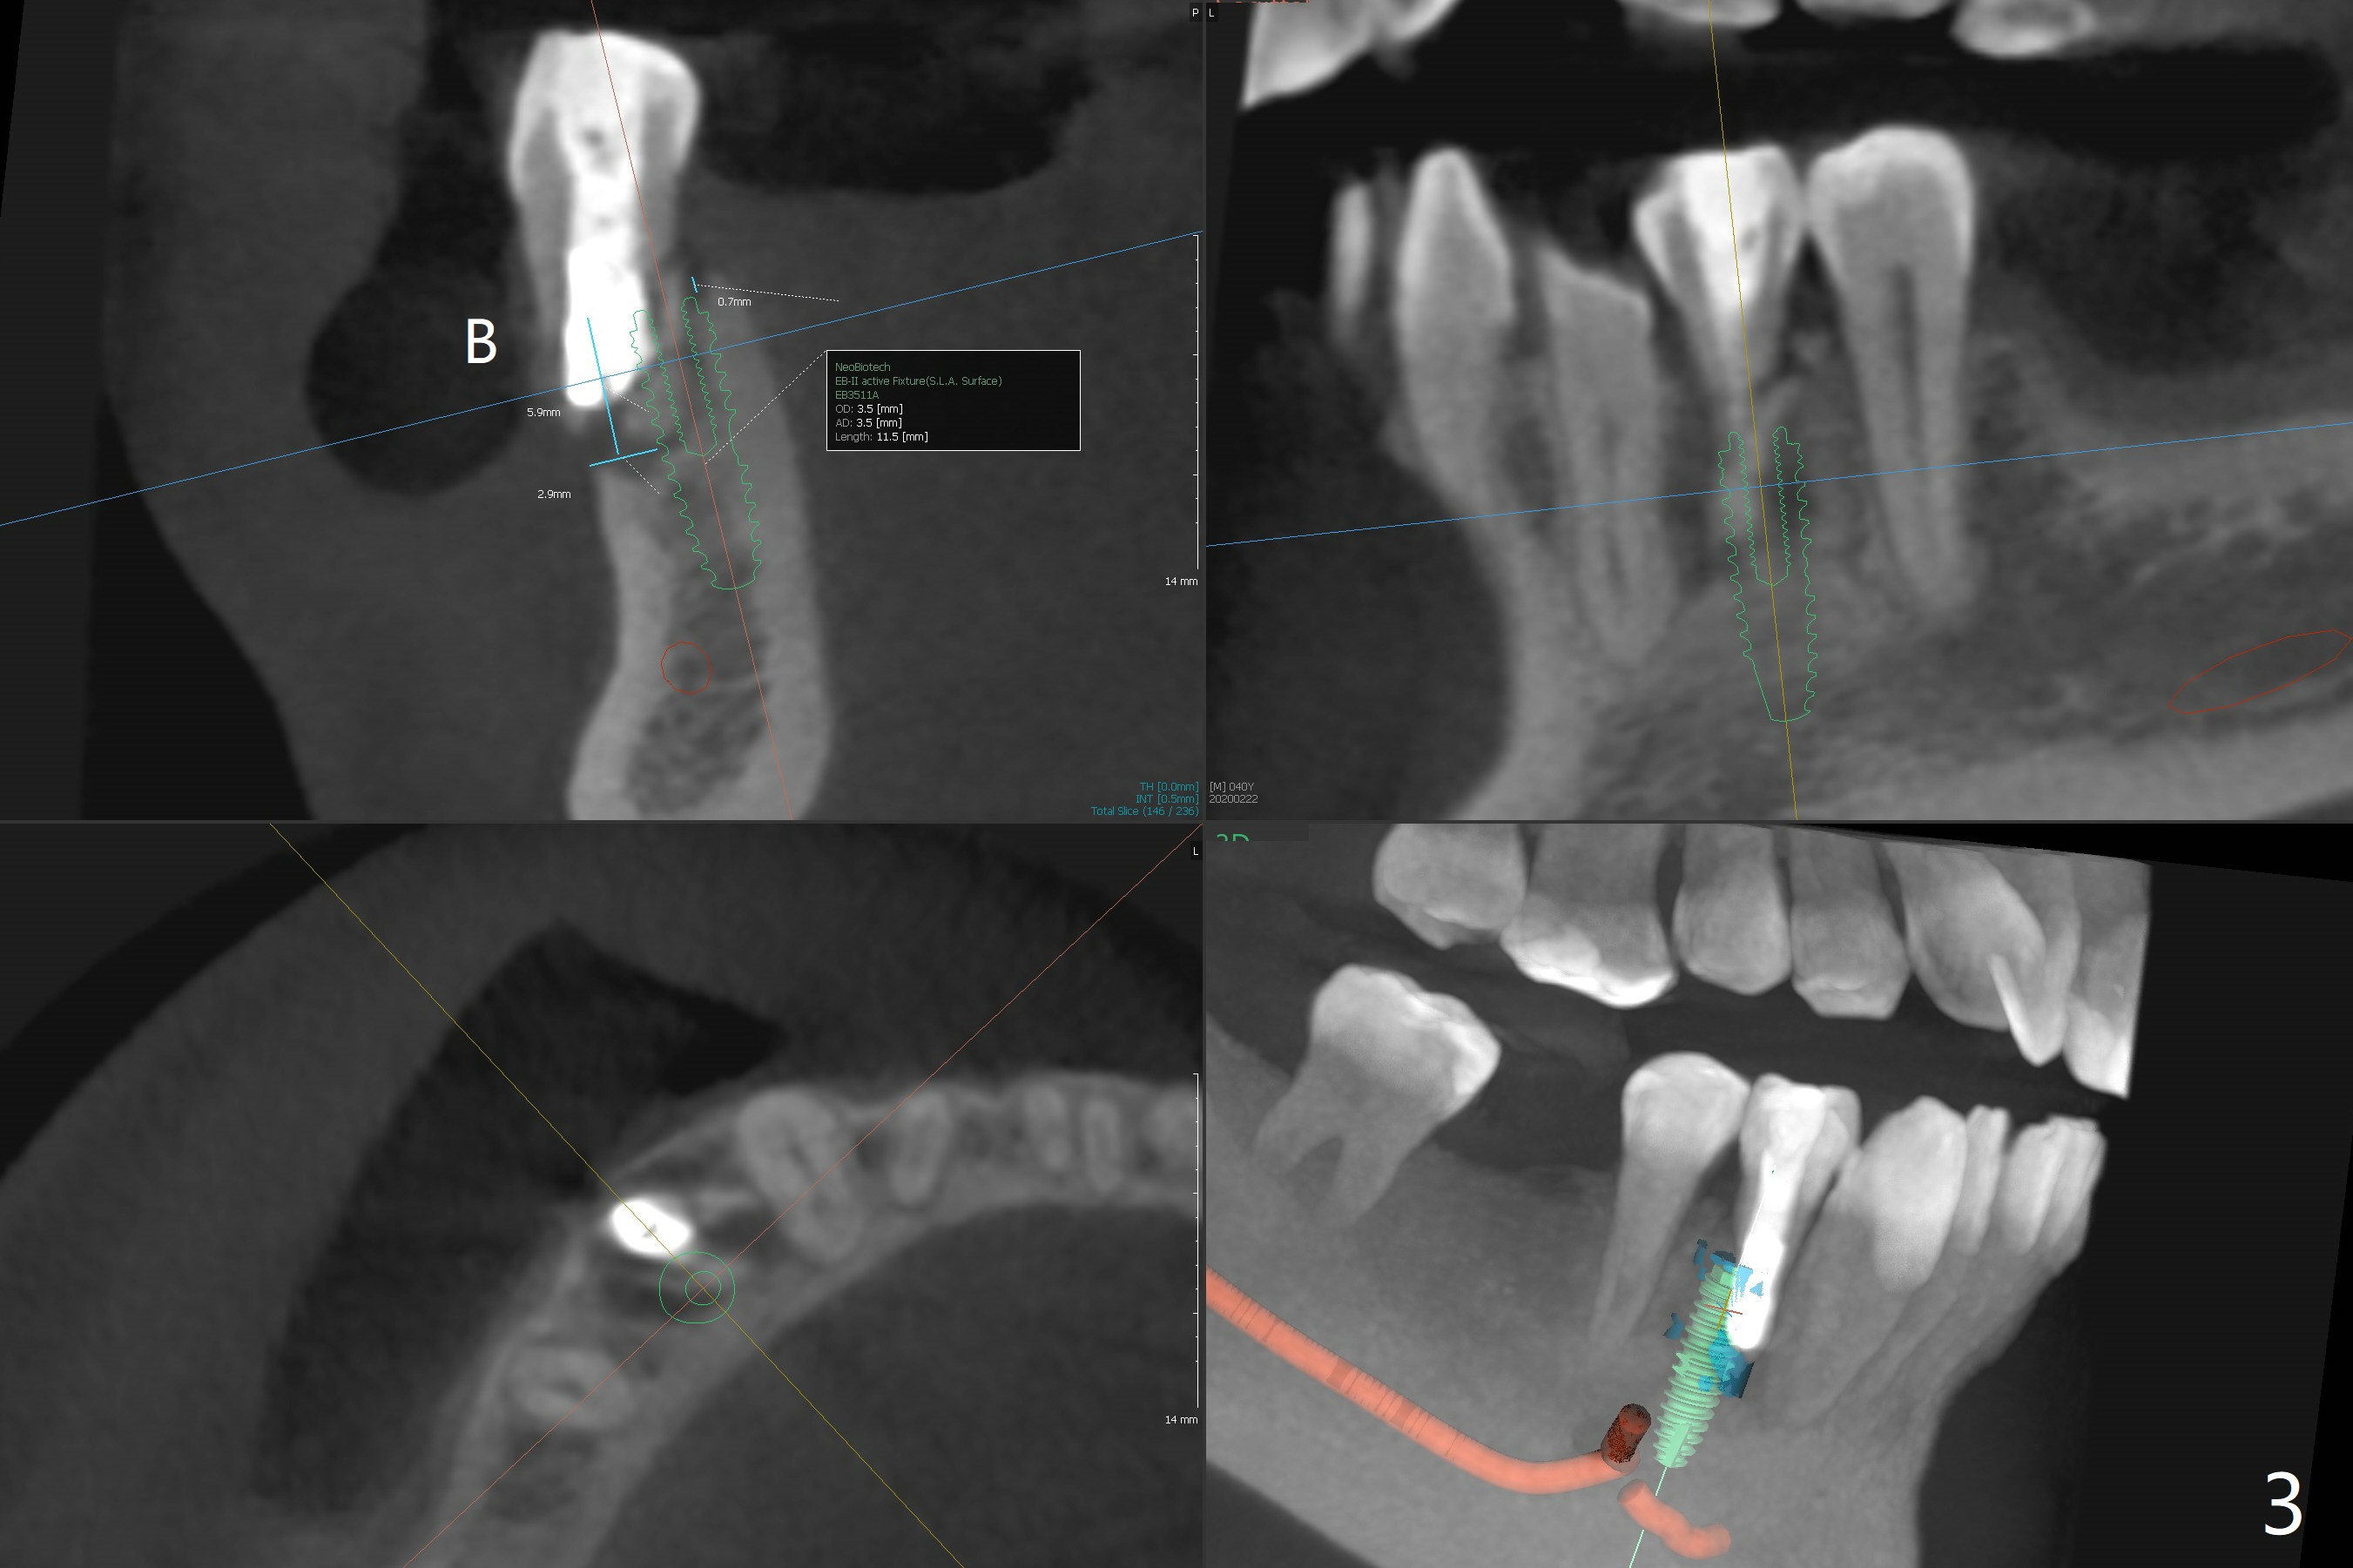

A -year-old man seeks treatment for the tooth #28 with severe bone loss (Fig.1 islands of bone remaining in the mesial surface of the tooth #27, reossification center for grafted bone). The tooth #28 has oblique root fracture (Fig.2 lingual view). One of treatment options is to place an immediate implant (green) at #28 as lingual as possible (Fig.3,4 (coronal section, after extraction (black area))). Sticky bone is placed buccal (Fig.5 red); some of bone graft will be pressed into the space between implant threads (arrowheads, bone and implant contact area expectedly to be higher than delayed placement due to less pressure to the native bone). In spite of severe bone loss between #27 and 28 (Fig.6 (sagittal section) after extraction), the crestal bone appears to exist in the mesial surface of #27 (*). With placement of an abutment (Fig.7 pink) and an immediate provisional (white), bone graft is packed as high as supracrestal (red). Restoration of the crest is expected to be better than socket preservation.

The ridge at #30 is narrow (~ 4 mm buccolingual and ~7 mm mesiodistal, Fig.8). A 4x11.5 mm will be placed. Impression will be taken for guides for #28 and 30. Incision will be made prior to guide seating (Fig.9 occlusal view); initial osteotomy (Fig.10 black circle) will be conducted with guide clockwise (white curved arrow). With removal of the guide, the ridge is split (Fig.11 black line). Osseocondensation drills will be used for ridge expansion with the help of guide (in the middle of the metal sleeve, Fig.12 counterclockwise).